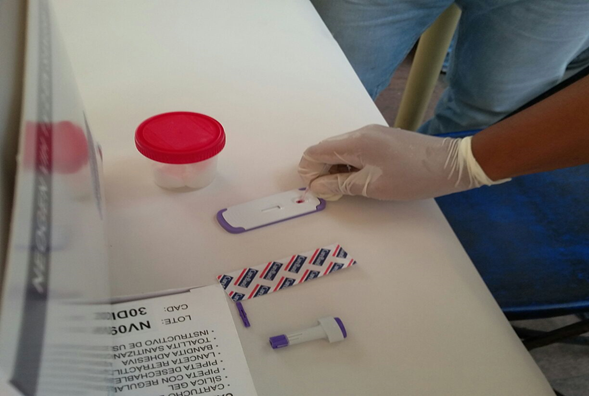

Se inauguró Primera Semana Nacional de Salud en Tres Valles

Alejandro Narváez, 25 de febrero de 2019

Nuevos casos de VIH en Coatzacoalcos

Tonantzin Zapata, 25 de febrero de 2019